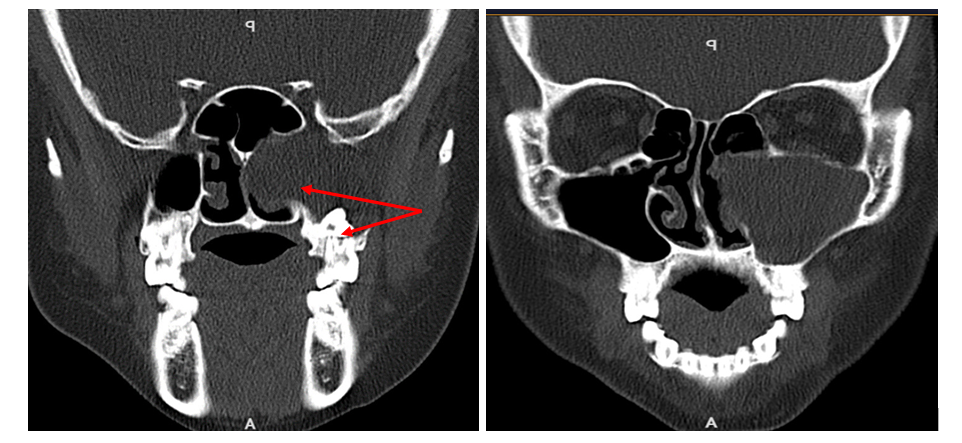

Recently, Ms.A had a stuffy nose and headache. Taking medicine did not help. The stuffy nose and headache gradually increased, so she went to Thai Nguyen International Hospital for examination. The patient was examined endoscopically, and the doctor concluded that he suspected a tumor in the left maxillary sinus. Patients were assigned CLS to confirm. The results of CT scan and magnetic resonance imaging (MRI) of the sinus system showed: The lesion in the left maxillary sinus, measuring 37x51mm, destroyed the sinus wall and invaded the left ethmoid sinus, pushing and shifting the nasal septum, there are also hidden teeth in the sinuses.

CT scanner and MRI images clearly show the tumor destroying the wall of the maxillary sinus pressure on the nasal septum and image of hidden teeth in the sinuses

After an interdisciplinary consultation with ENT and Maxillofacial specialists, the doctors concluded: The patient has a left maxillary sinus tumor with teeth growing underground in the sinus that has destroyed the wall of the maxillary sinus, which can affect the near tissues. Diagnosis conclusion: Dental cyst. This is a rare medical case with bone destruction and requires early surgery to avoid dangerous complications. The patient was prescribed surgery to open the maxillary sinus to remove the tumor combined with the extraction of hidden teeth in the sinus. The surgery was performed simultaneously by two surgical teams: Ear-Nose-Throat and Dentistry-Maxillofacial specialists. Determining that this was a complex surgery, the surgical team chose to operate in two ways, combining endoscopic sinus surgery and opening the left maxillary sinus according to the Caldwell-Luc route to expand the surgical field to perform both at the same time to save medical costs and treatment time.